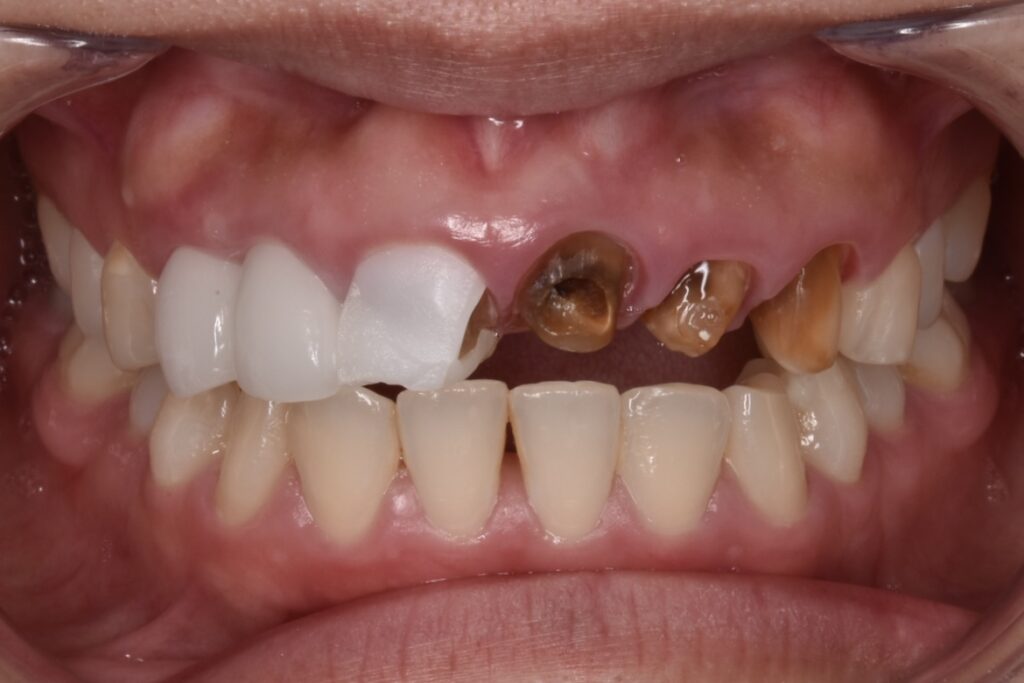

初診時の状態

白い6連結のセラミックがありますが、右側のセラミックの前歯は破折しています。(写真左)また6連結の中央でジルコニアのフレームごと破折していることも確認できます。(写真中央)左の前歯は神経処置がされておらず穴だけ開いた状態でした。(神経治療途中?)土台6本全てが茶色から黒色に変色している事が周囲の天然歯と比べてもわかります。